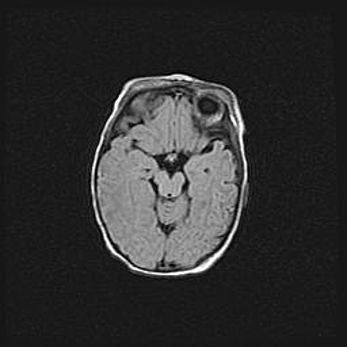

Сообщающаяся гидроцефалия. Кистозная энцефаломаляция головного мозга.

Возраст: 3 месяца 4 дня

Вес: 3100 г

Пол: женский

Окружность головы: 34 см

Срок гестации: 31 неделя

Кистозная энцефаломаляция головного мозга - одна из форм поражения головного мозга в детском возрасте. Характеризуется возникновением множественных и распространённых кист в коре, белом веществе и подкорковых образованиях головного мозга у плодов, новорождённых и детей раннего возраста. Развитие кистозной энцефаломаляции связано с внутриутробной асфиксией и гипотонией, родовой травмой, тромбозом синусов, пороками развития сосудов, инфекциями, сепсисом и другими причинами. Наиболее значимые инфекционные агенты: вирусы простого герпеса, цитомегалии, краснухи, токсоплазмы, энтеробактерии, золотистый стафилококк и другие.